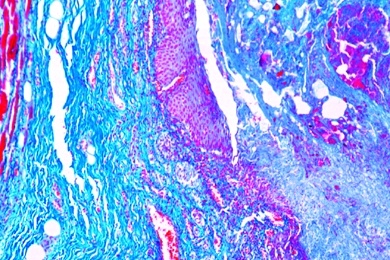

Mikropräparate in Serie - Pathologische Histologie des Menschen, Basisserie, 50 Präparate mit Begleittext

Pathologische Histologie des Menschen, Basisserie 50 Präparate mit ausführlichem Begleittext,

Unsere Mikropräparate werden unter wissenschaftlicher Leitung hergestellt. Sachgemäß fixiertes und konserviertes Ausgangsmaterial ist die Voraussetzung für einwandfreie Präparate. Wir verwenden deshalb auf diese Arbeitsgänge besondere Sorgfalt. Die Herstellung der Mikrotomschnitte erfolgt durch erfahrene Fachkräfte, Schneidetechnik und Schnittdicke werden den Objekten angepaßt. Aus der großen Zahl der in der Mikroskopie üblichen Färbemethoden wählen wir solche, die eine klare und kontrastreiche Darstellung der gewünschten Strukturen mit bester Haltbarkeit verbinden. Meist handelt es sich dabei um Mehrfachfärbungen.